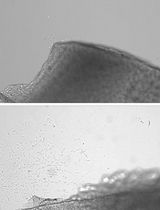

Murine Pancreatic Islets Transplantation under the Kidney Capsule

Cover of Diabetes, featuring study using the protocol.